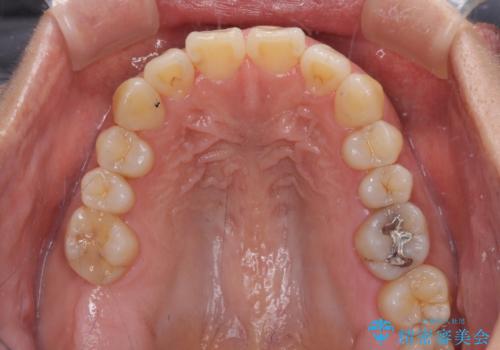

- 上下前歯の叢生を気にして来院された患者様です。

費用を抑え、期間もあまりかけずに治療をしたいとのことで、インビザライン・ライトを用いて矯正治療を行うこととしました。

インビザライン・ライトは、製作できるアライナーの枚数に制限があるため、移動可能な量に限りがあります。

一方で、半年から1年程度で治療を終えることができるため、軽度の歯列不正の患者様には大変お勧めです。